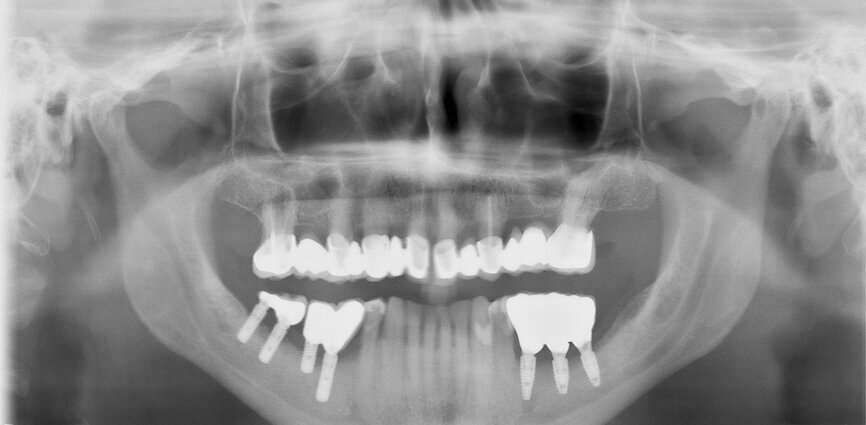

Fig. 14: Dental panoramic tomogram of initial situation.

The first was a 51-year-old patient who smoked 30 cigarettes per day and suffered from diabetes and stress (Figs. 1–8). The second was a 76-year-old male patient in good physical condition who smoked 40 cigarettes per day. He underwent reconstruction of the premaxilla (Figs. 9–13). The third was a healthy female patient of 24 years of age who smoked 20 cigarettes per day. She required a sinus lift in region #25 (Figs. 14–21). The patients were informed of the intended process in detail and signed the surgical protocol containing information concerning possible risks of failure and complications, as well as information on the alloplastic and synthetic materials to be used.

Digital radiographic images were taken at the time of surgery, 24 hours postoperatively and one month later in order to evaluate implant success (Figs. 6, 7, 11, 13, 15 & 20). In none of the patients inflammatory processes were found and all implants remained stable.